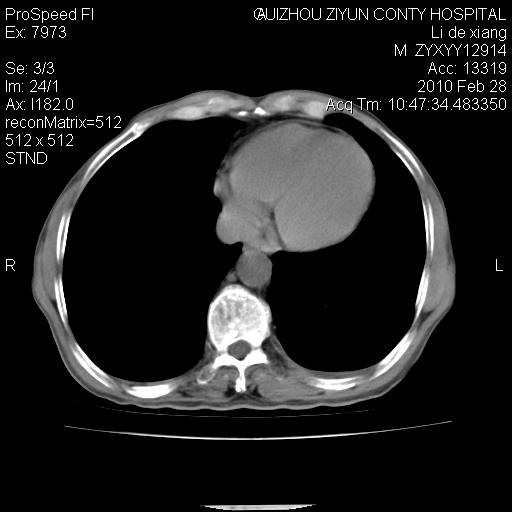

标题: CT24776:男 71Y 咳嗽咳痰胸痛两月,伴声音嘶哑。 [打印本页]

标题: CT24776:男 71Y 咳嗽咳痰胸痛两月,伴声音嘶哑。

左侧中央型肺癌伴左肺上叶阻塞性肺炎及节段性不张可能性大,建议纤支镜检查!

左侧中央型肺癌伴左肺上叶阻塞性肺炎及节段性不张可能性大,建议纤支镜检查!纵隔淋巴结转移.

左侧中央型肺癌伴左肺上叶阻塞性肺炎及纵隔淋巴结转移。

左肺门部肿块,伴左上肺斑块影,周边模糊,支持左肺中央型肺癌伴节段性不张及阻塞性肺炎,结合支气管镜检查。

患者有声音嘶哑,若时间长了,没改变,喉镜检查无异常,可考虑左侧喉返神经受累,因为:左侧喉返神经绕主动脉弓或肺动脉韧带的主动脉端,沿气管与食管之间的沟上行至颈部.

左上叶支气管狭窄,阻塞性病变,肺门肿块,纵隔及肺门淋巴结增大,中央性肺癌